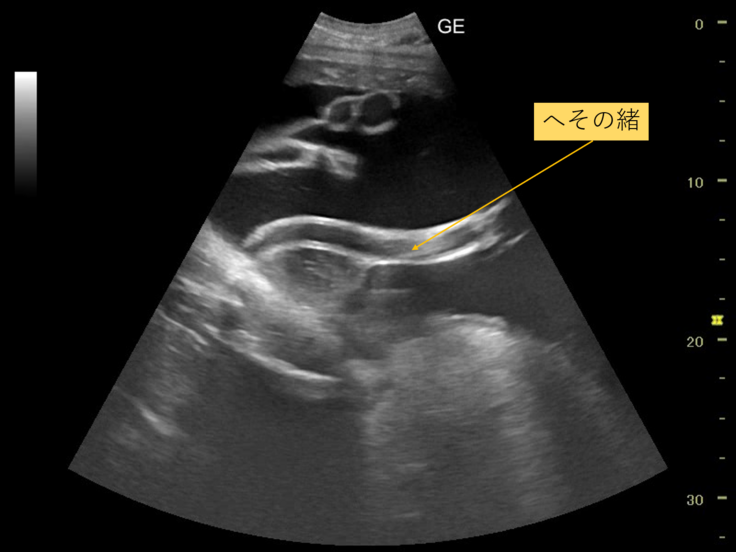

昨日1月8日に、メイのお腹の超音波検診を行いましたので、その様子を紹介します。

肝心の検査結果ですが、今回の検査では、胎児は超音波で見える範囲でじっとしてくれず、様子をはっきりと見ることはできませんでした。

ですが、へその緒の様子は確認できました。